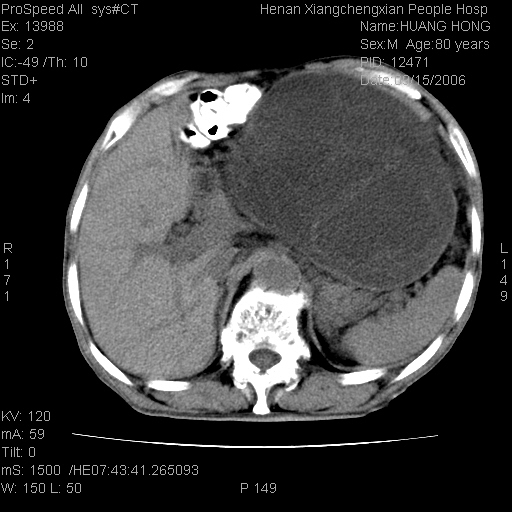

患者, 男, 80岁, 发现上腹部包块1年余,无其它不适.2006-9-14ct片是喝水后扫描2006-9-15ct片没喝水扫描![]() ![]() ![]() ![]() ![]() ![]() ![]() ![]() ![]() ![]() ![]() ![]() ![]() ![]() ![]() ![]() 以上是喝水片 以下是空腹片 ![]() ![]() ![]() ![]() ![]() ![]() ![]() ![]() ![]() ![]() ![]() ![]() ct:胰腺前方、肝脏与胃之间可见巨大类圆形囊性低密度影,大小约152mmx145mmx118mm,上缘平t11椎体上缘,下缘平l3椎体下缘,密度均匀,ct值15hu,其内呈多房分隔,囊壁薄且光滑,边界清晰,周围组织及器官明显受压。肝脏实质内未见异常密度影,胆囊未见异常,胰腺密度未见异常,脾脏大小、形态及密度未见异常,腹膜后间隙未见肿大淋巴结影。 印象:胰腺前方、肝脏与胃之间巨大类圆形囊性低密度影.性质待定。多考虑:.肠系膜巨大囊肿。 守望可可西里发言:支持楼主,考虑肠系膜囊肿,多为小肠系膜。 ysxyy发言:我总觉得这个病人虽然很像肠系膜囊肿,但还是应该强化一下; 下面这几幅图里肿块和主动脉的关系不太清,不知能否除外血管性来源? ![]() ![]() ![]() 病理结果:横结肠系膜间叶瘤.部分区域间质细胞增生活跃. 病理图片 ![]() 良性间叶瘤:是指由两种或两种以上的间叶组织所构成的混合性肿瘤.肿瘤仅发生在腹膜后和肠系膜,.前者较后者多发.良性间叶瘤常发生在肾或四肢,腹膜后较少见,各年龄均可发病.女多与男,预后较好,但术后易复法. 恶性间叶瘤:由两种以上恶性间叶组织成分组成. 光镜:肿瘤由脂肪/血管/平滑肌构成. 原贴地址: http://www.radinet.com.cn/forum_view.asp?forum_id=4&view_id=16217 ok |